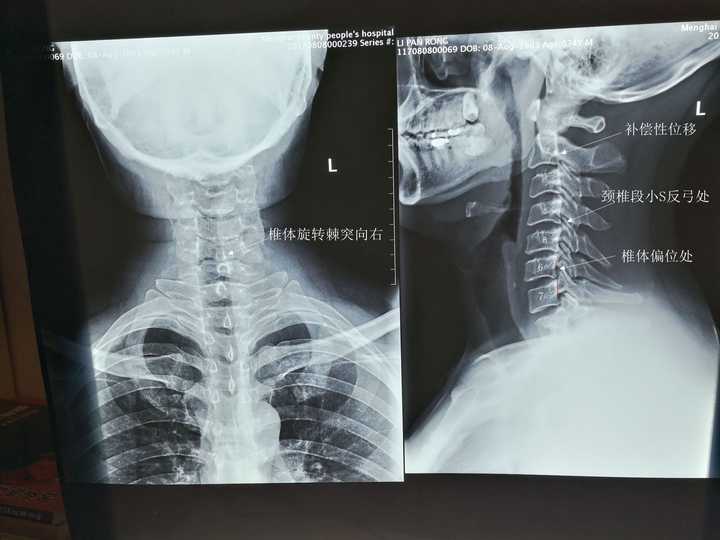

颈椎摄影,颈椎

术前颈椎过伸过屈动力位片

颈椎

颈椎突出

正常颈椎

颈椎解剖

颈椎部位图

颈椎解剖图

正常颈椎图片

颈椎结构图

颈椎图片构造图解高清